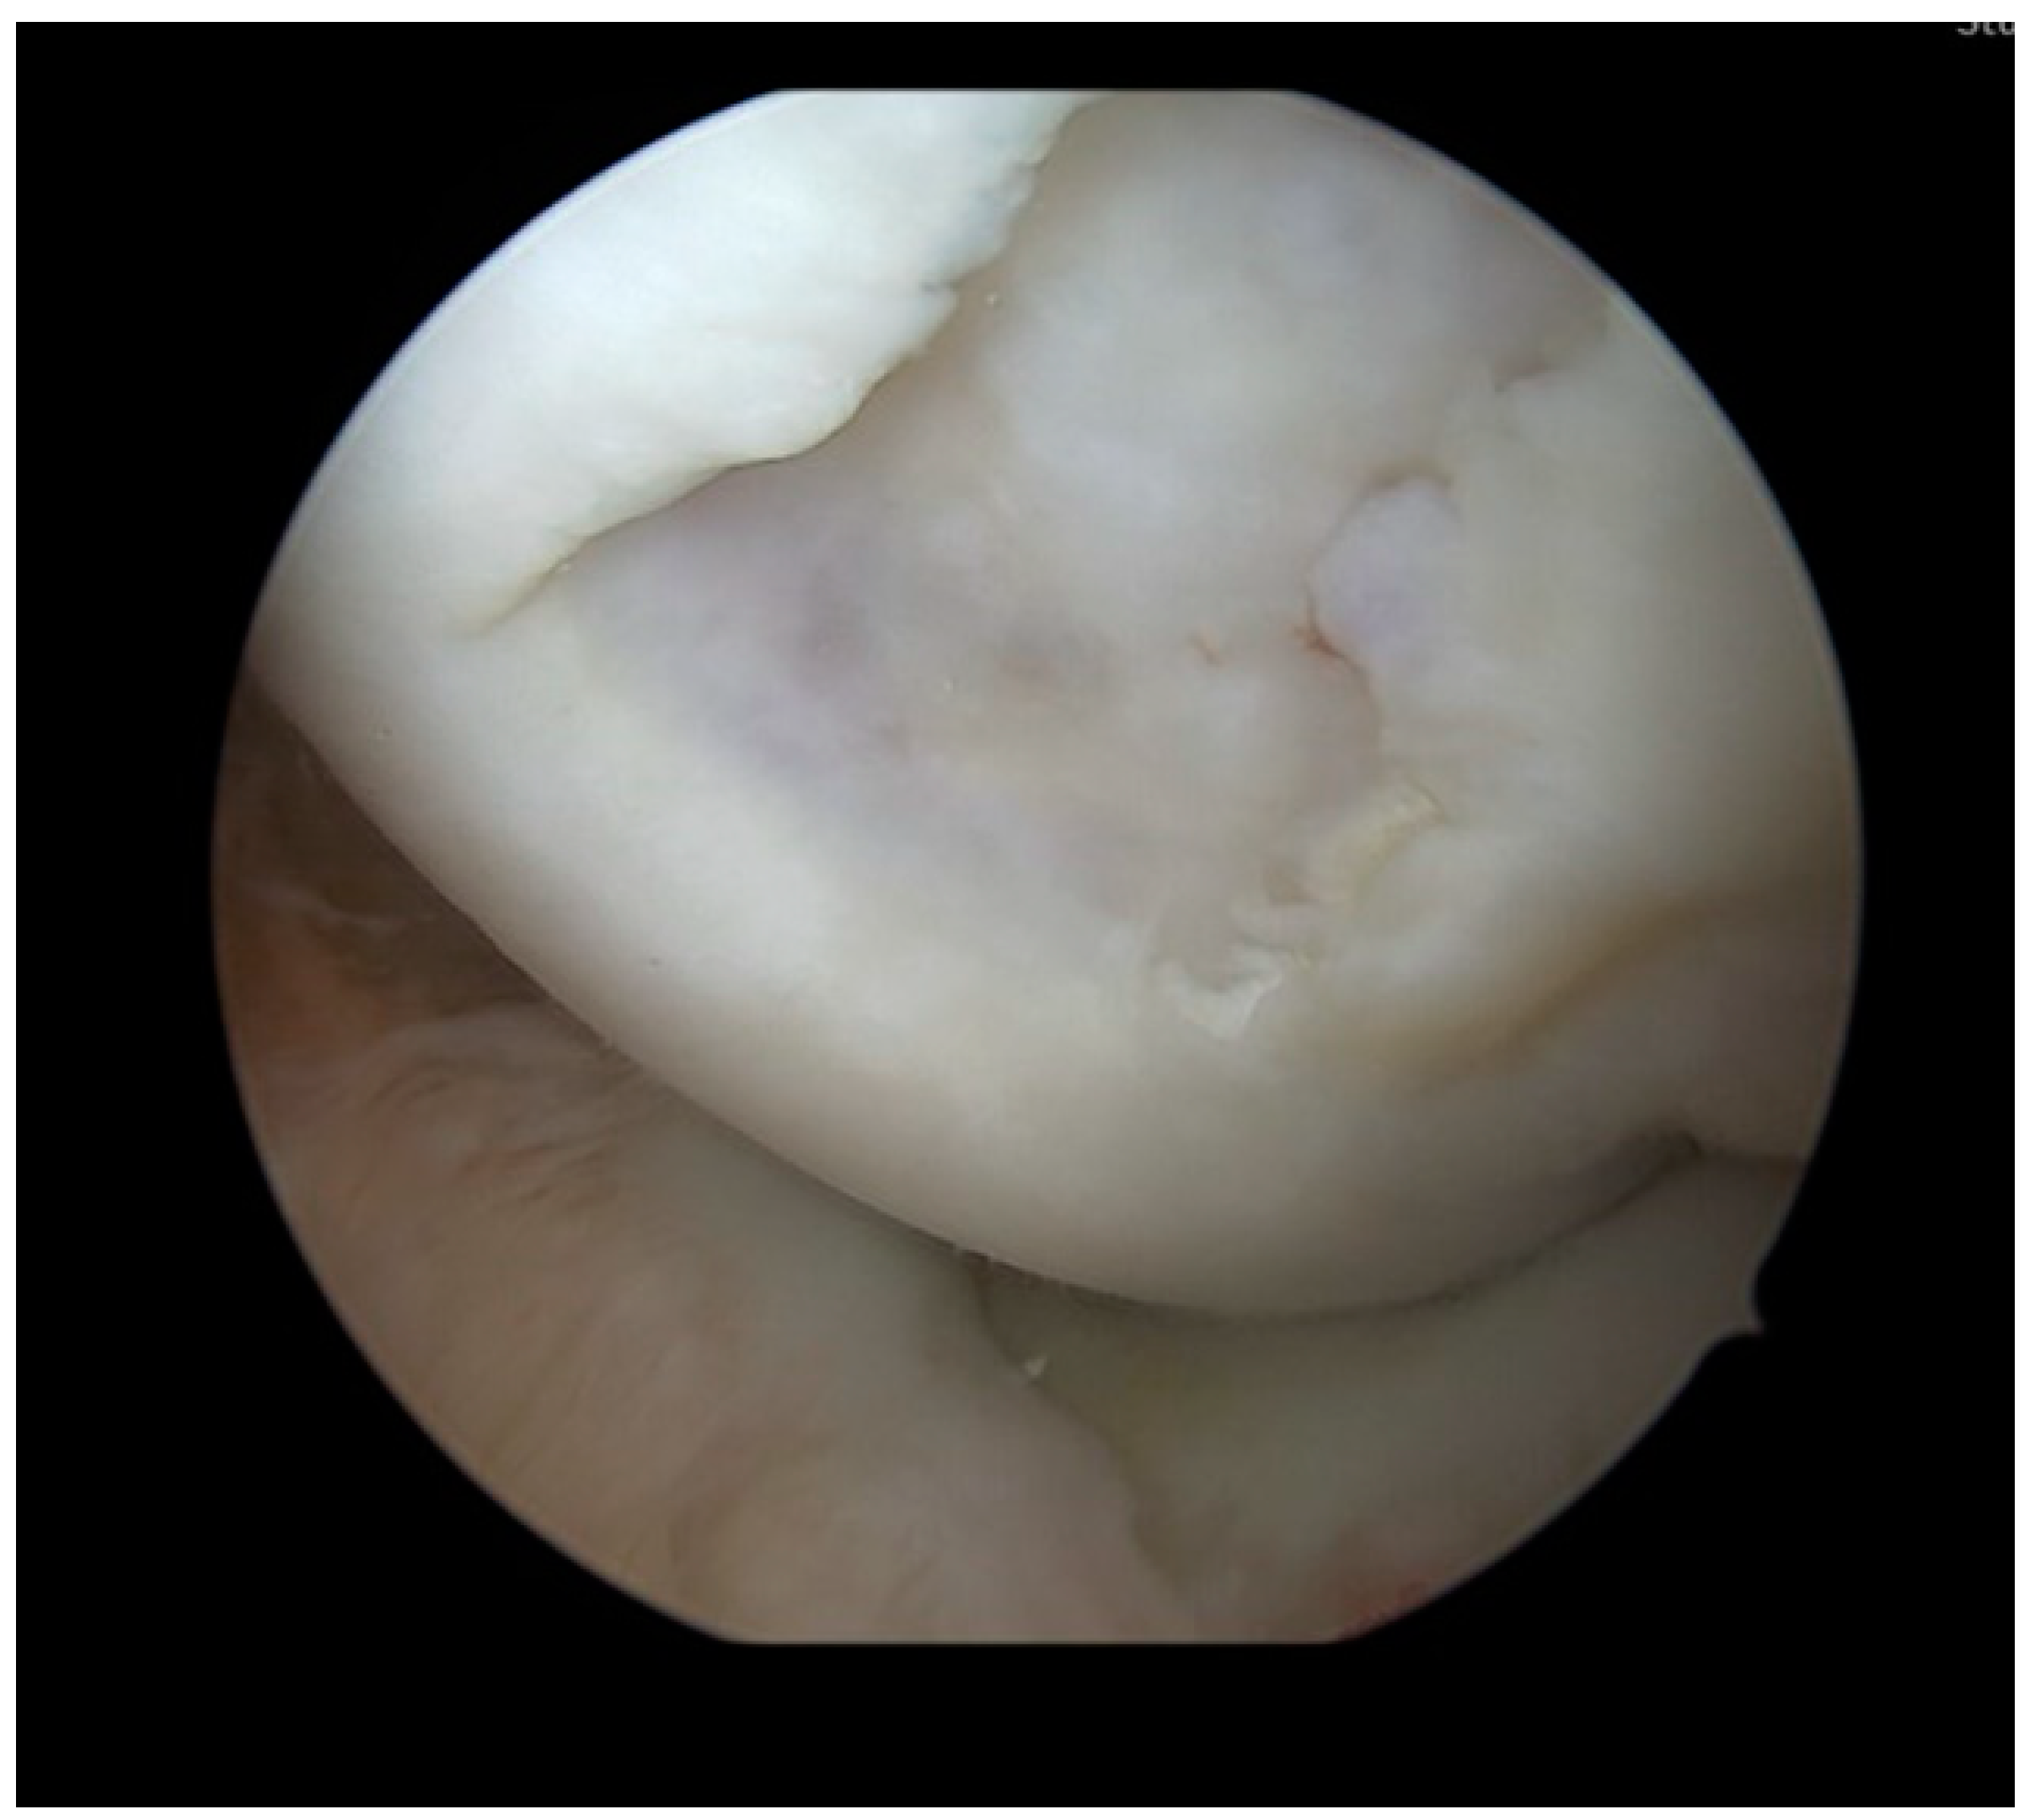

2. Case Report